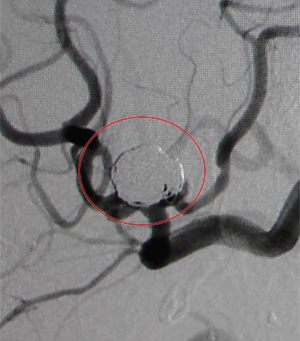

コイル塞栓手術前

コイル塞栓手術後